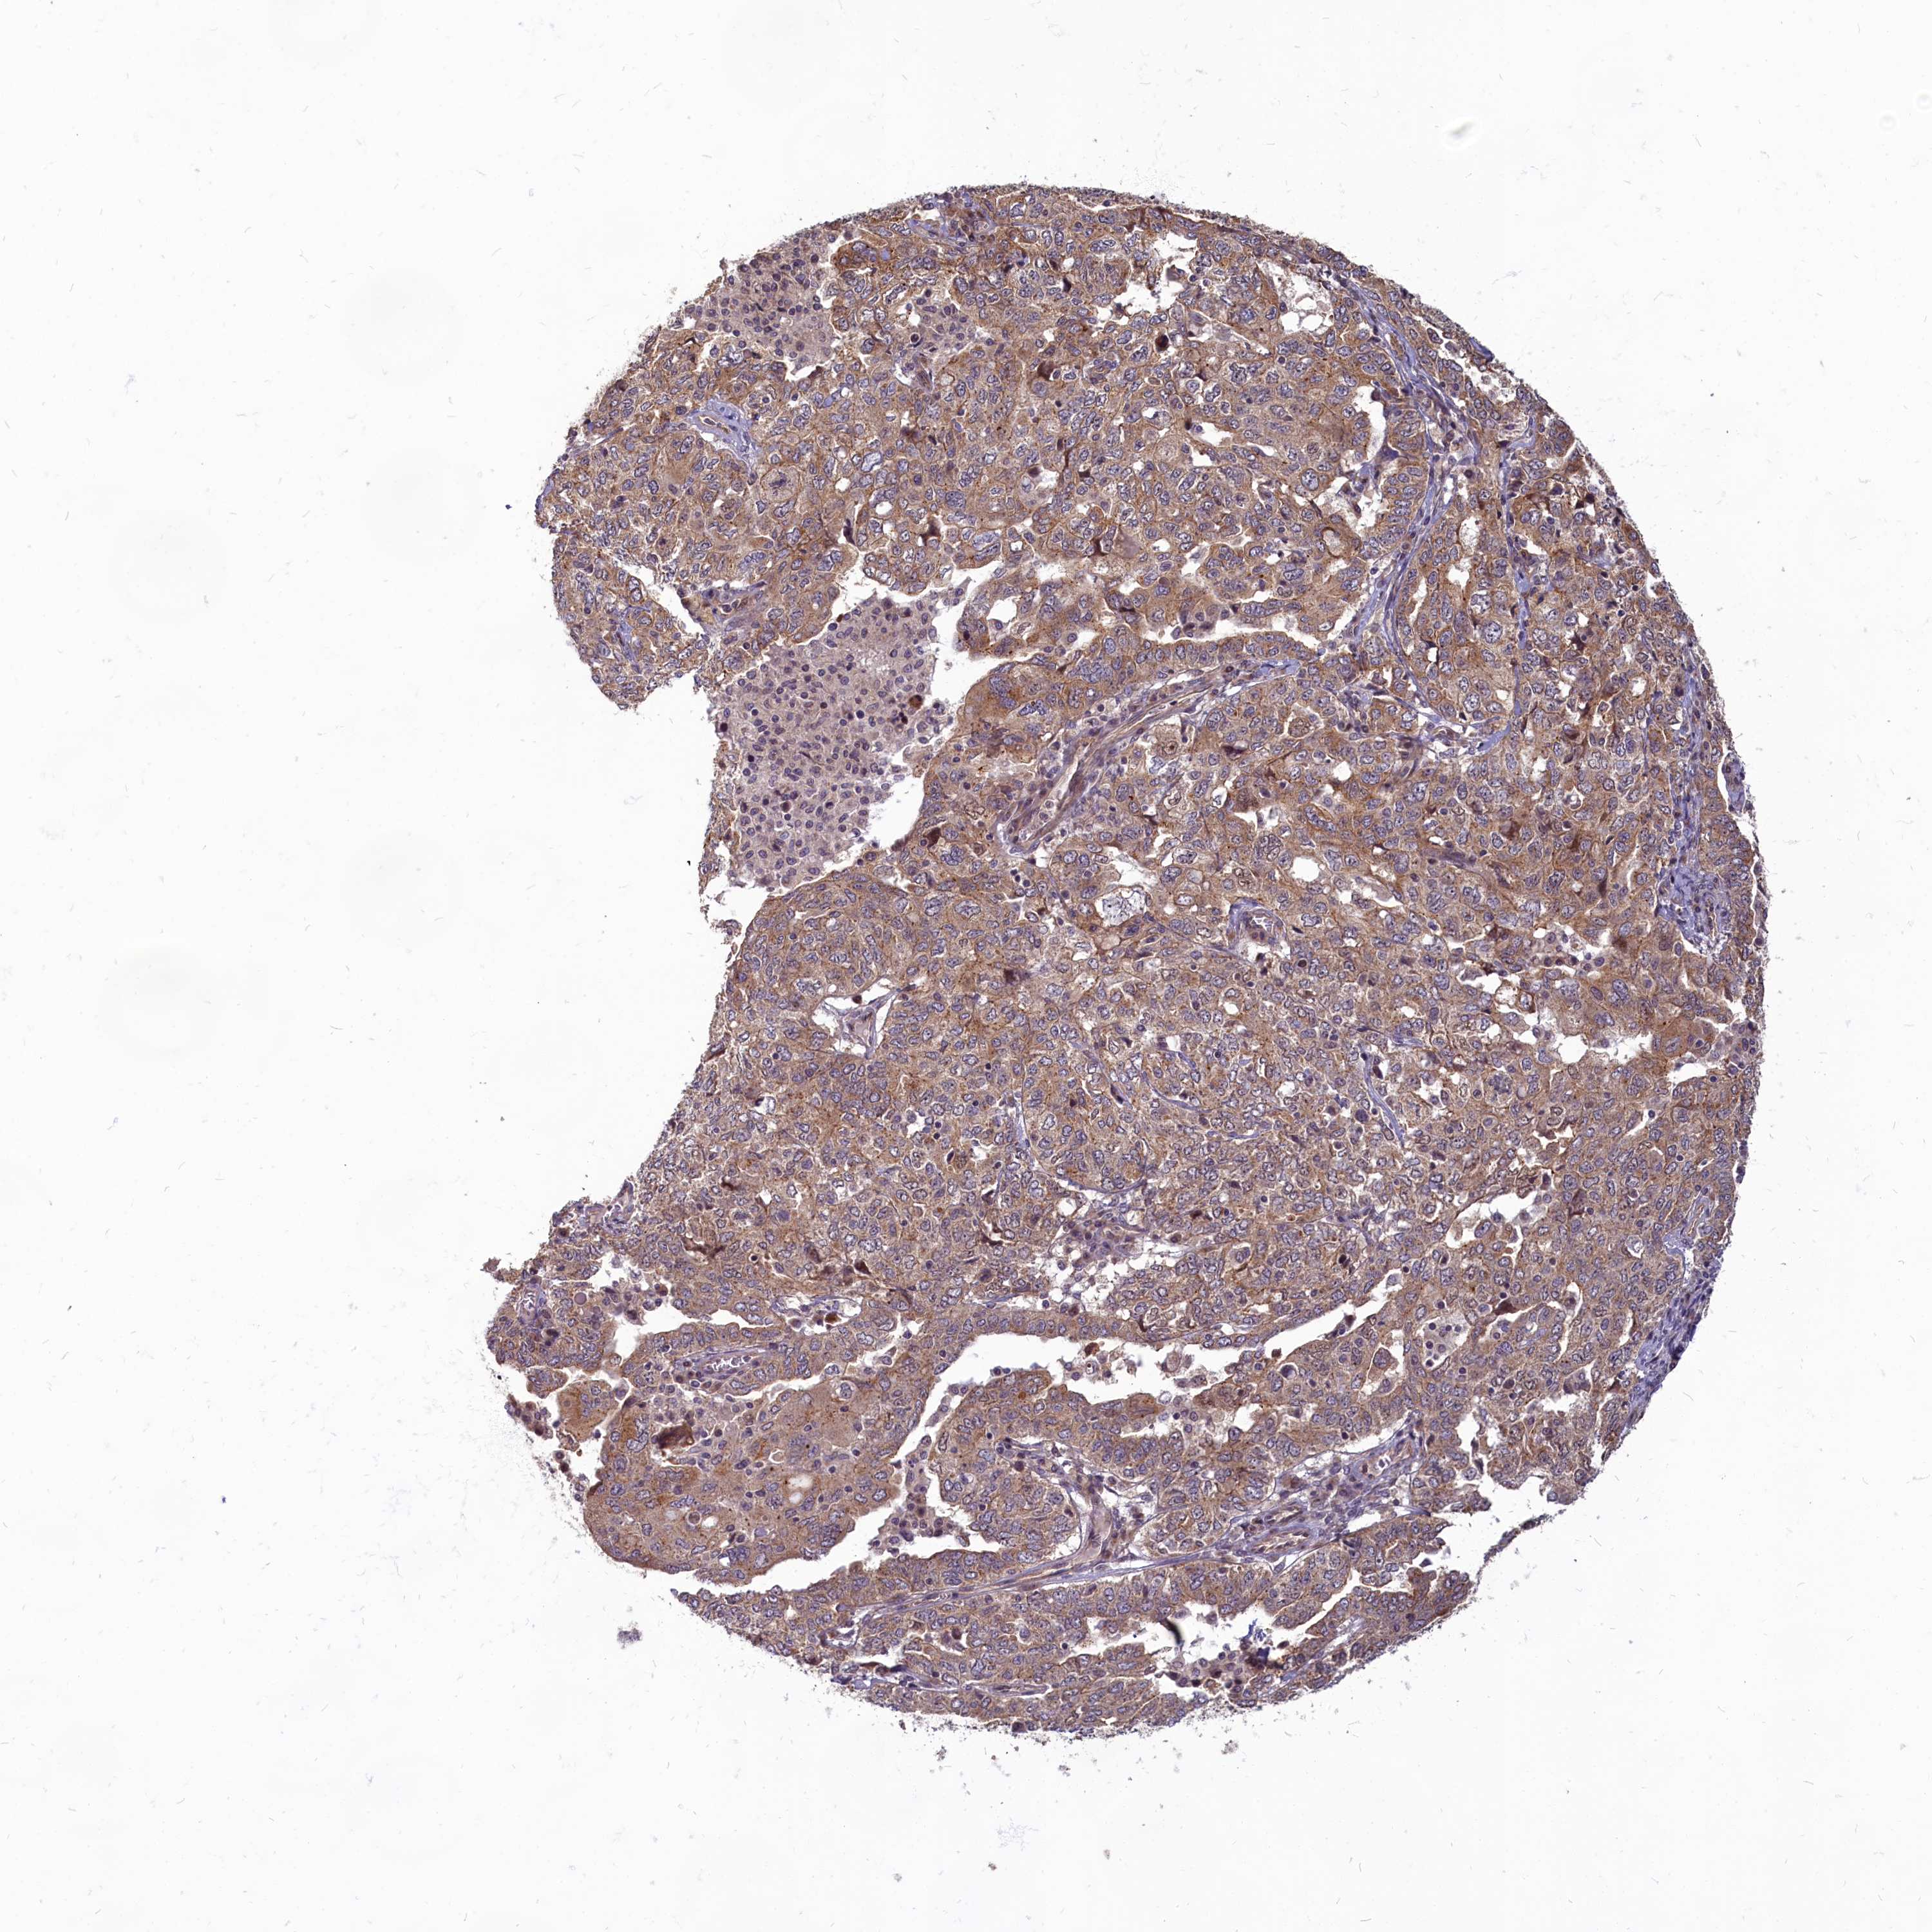

OVARIAN CANCER - Protein expressioni

A mouse-over function shows sample information and annotation data. Click on an image to view it in a full screen mode. Samples can be filtered based on level of antibody staining by selecting one or several of the following categories: high, medium, low and not detected. The assay and annotation is described here.

Note that samples used for immunohistochemistry by the Human Protein Atlas do not correspond to samples in the TCGA dataset.

Antibody stainingi

Antibody staining in the annotated cell types in the current human tissue is reported as not detected, low, medium, or high, based on conventional immunohistochemistry profiling in selected tissues. This score is based on the combination of the staining intensity and fraction of stained cells.

Each image is clickable and will lead to virtual microscopy that enables deeper exploration of all samples and also displays staining intensity scores, fraction scores and subcellular localization as well as patient and tissue information for each sample.

Antibody HPA041188

Staining

High

Medium

Low

Not detected

Intensity

Strong

Moderate

Weak

Negative

Quantity

>75%

75%-25%

<25%

None

Location

Nuclear

Cytoplasmic/membranous

Cytoplasmic/membranous,nuclear

Cystadenocarcinoma, serous, NOS

Carcinoma, endometroid

Cystadenocarcinoma, mucinous, NOS

Carcinoma, NOS